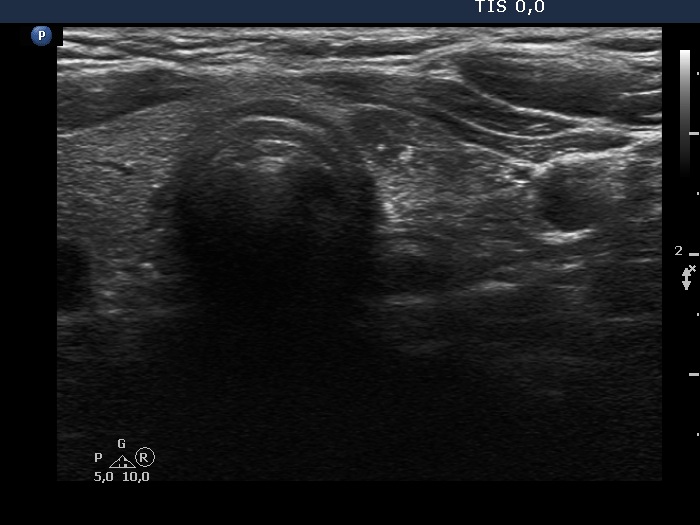

Ultrasonography. The thyroid was echonormal. Beside several hypoechoic and cystic lesions without any clinical significance, both lobes had a hypoechoic nodule. The presentation of them was very similar, both had echogenic granules and showed peripheral vascularity. However, the echogenic figures in the right nodule were probably back wall figures while those in the left nodule were microcalcifications. Regarding the vascularity, the left nodule showed perinodular blood flow while the right did not.

Comment. It is worth comparing the ultrasound presentations of the two nodules. There are small but important differences between them regarding the echogenic figures and the vascularity.